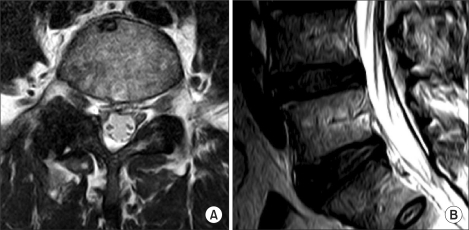

MRI showing L4-5 synovial cyst compressing the thecal sac and right nerve root. Sagittal (left) and axial (right) T2-weighted views demonstrating the cyst arising from the facet joint.

MRI Features That Predict Success

Favorable features (higher rupture success):

• T2 hyperintense (bright): Indicates fluid-filled cyst — more likely to rupture

• Thin wall: Less resistance to pressurization

• Acute/subacute onset: Weeks to a few months of symptoms

IPSIS specifically describes favorable and unfavorable MRI features:

Favorable for rupture:

• T2-hyperintense signal (similar to CSF) indicating fluid content

• Thin wall without obvious internal structure

• No calcification or inspissated material